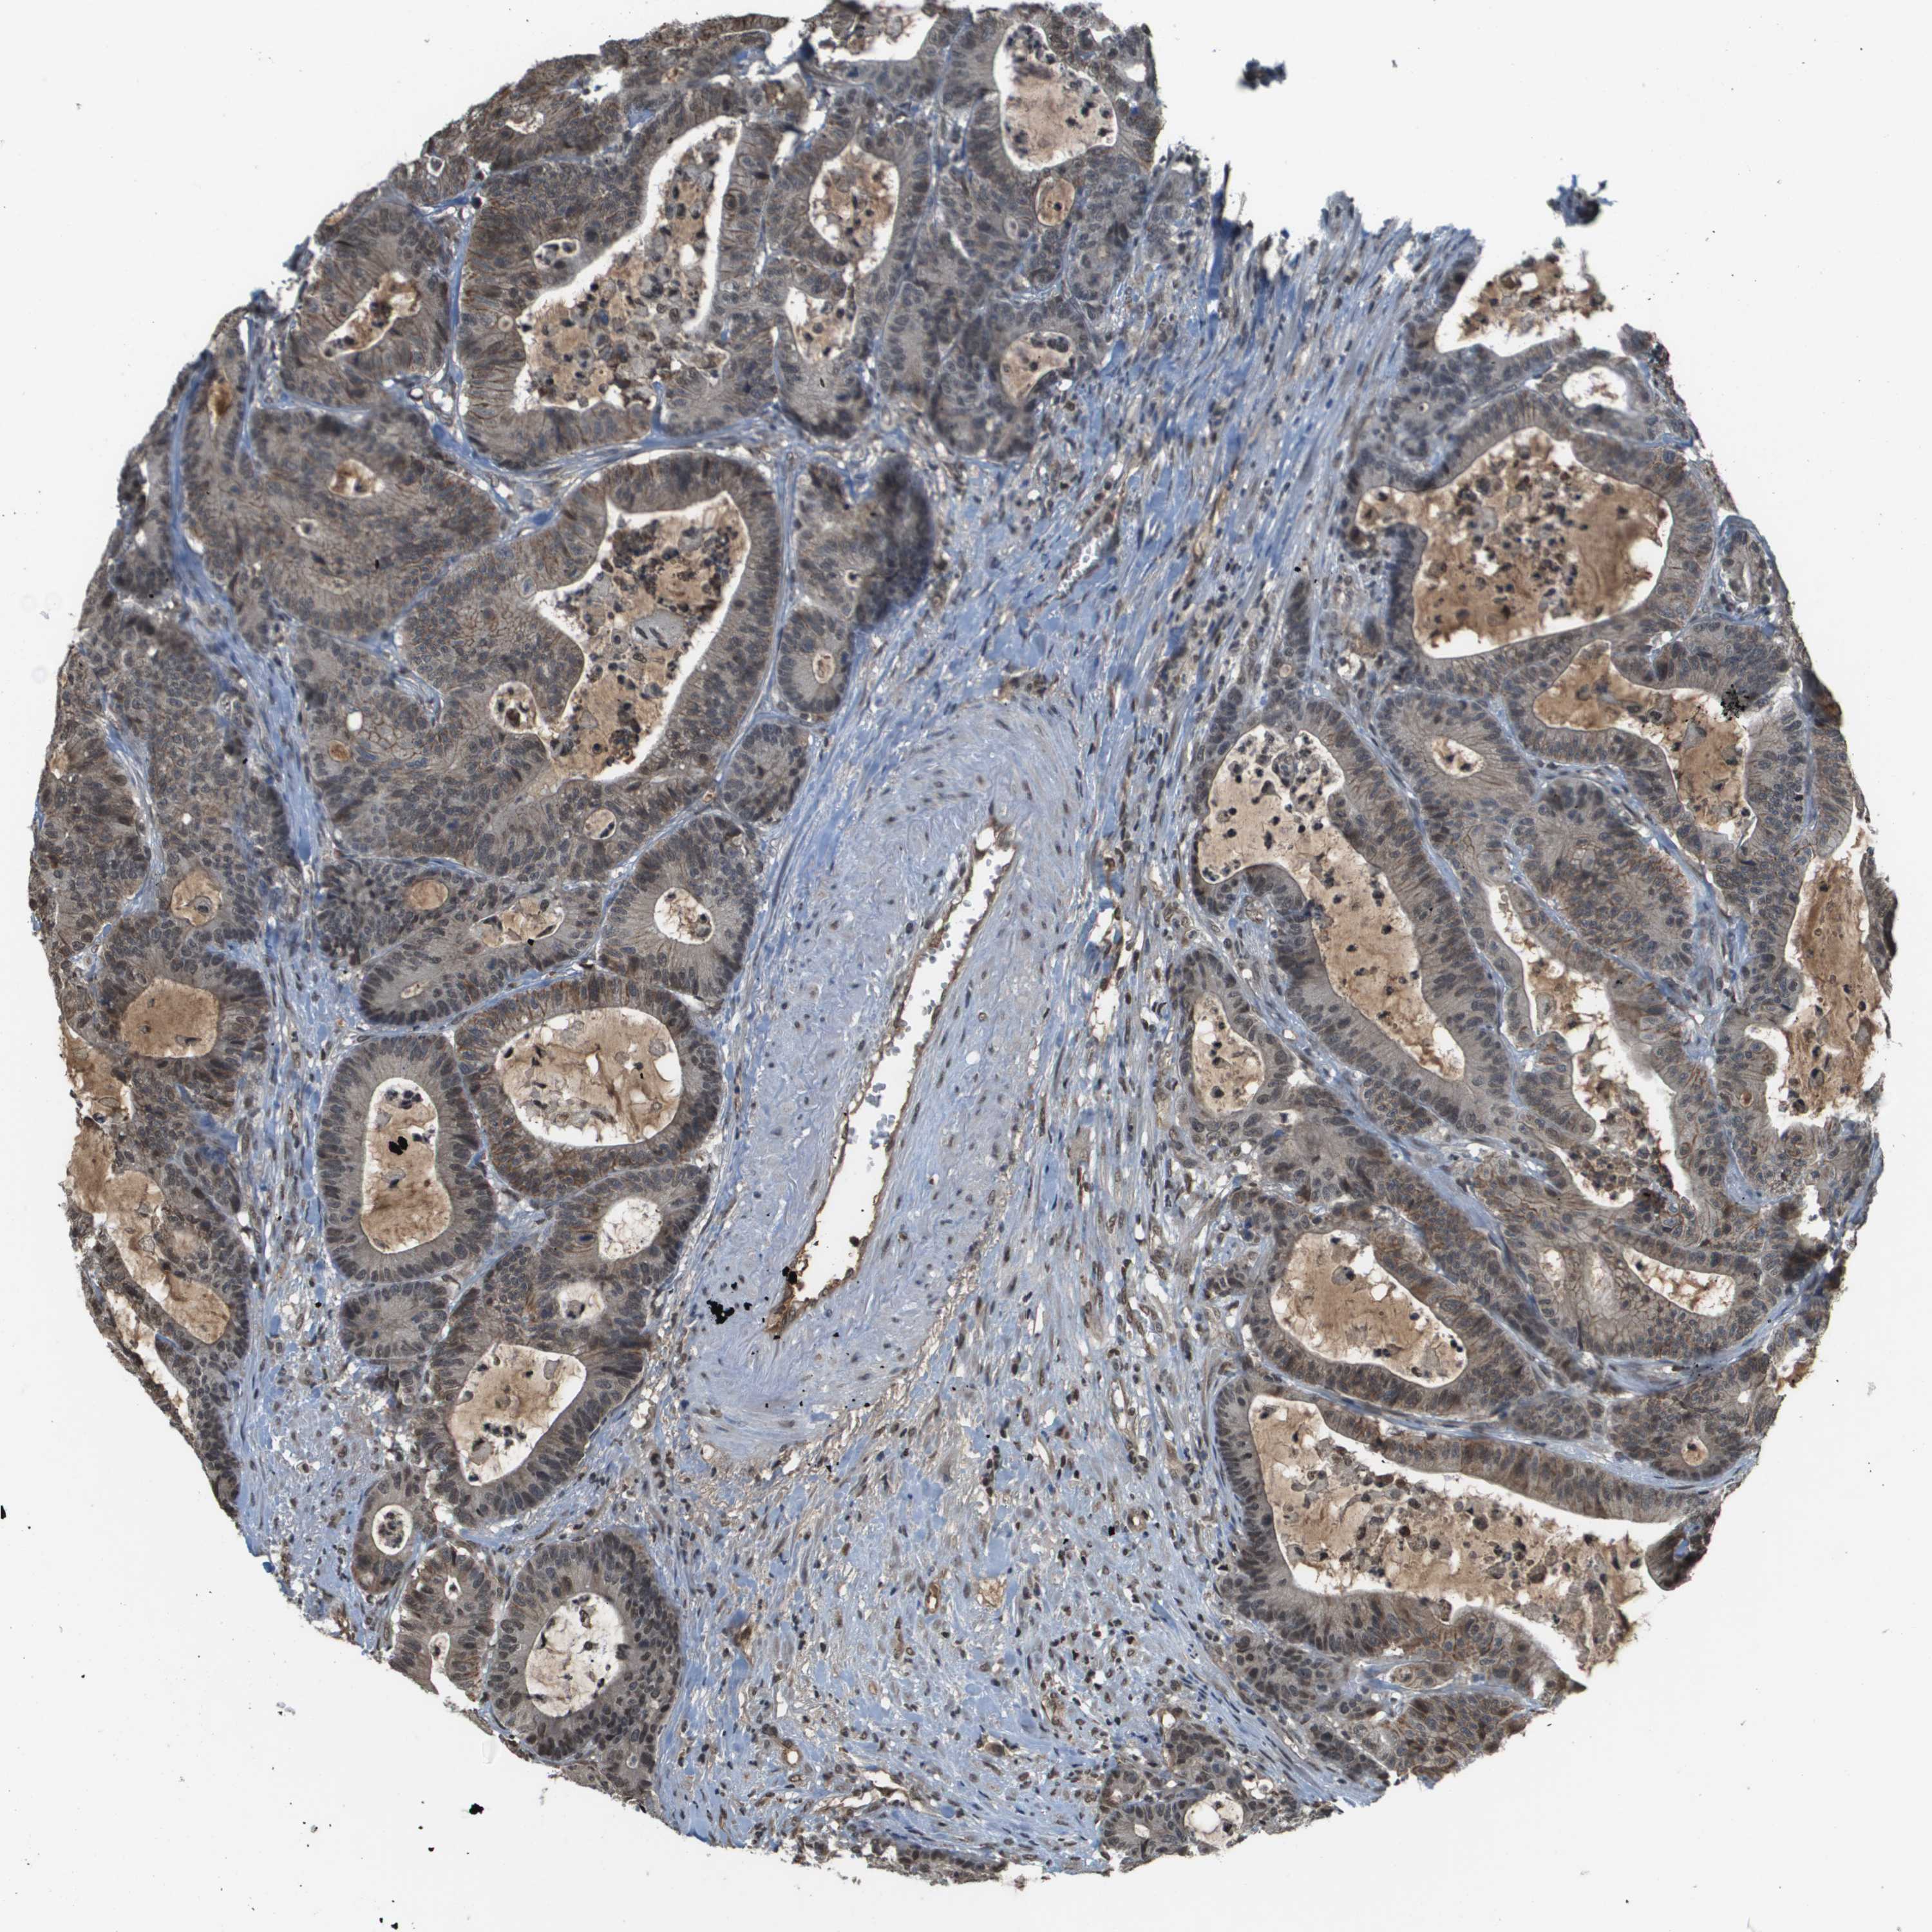

ANTIBODIES

AND

VALIDATION